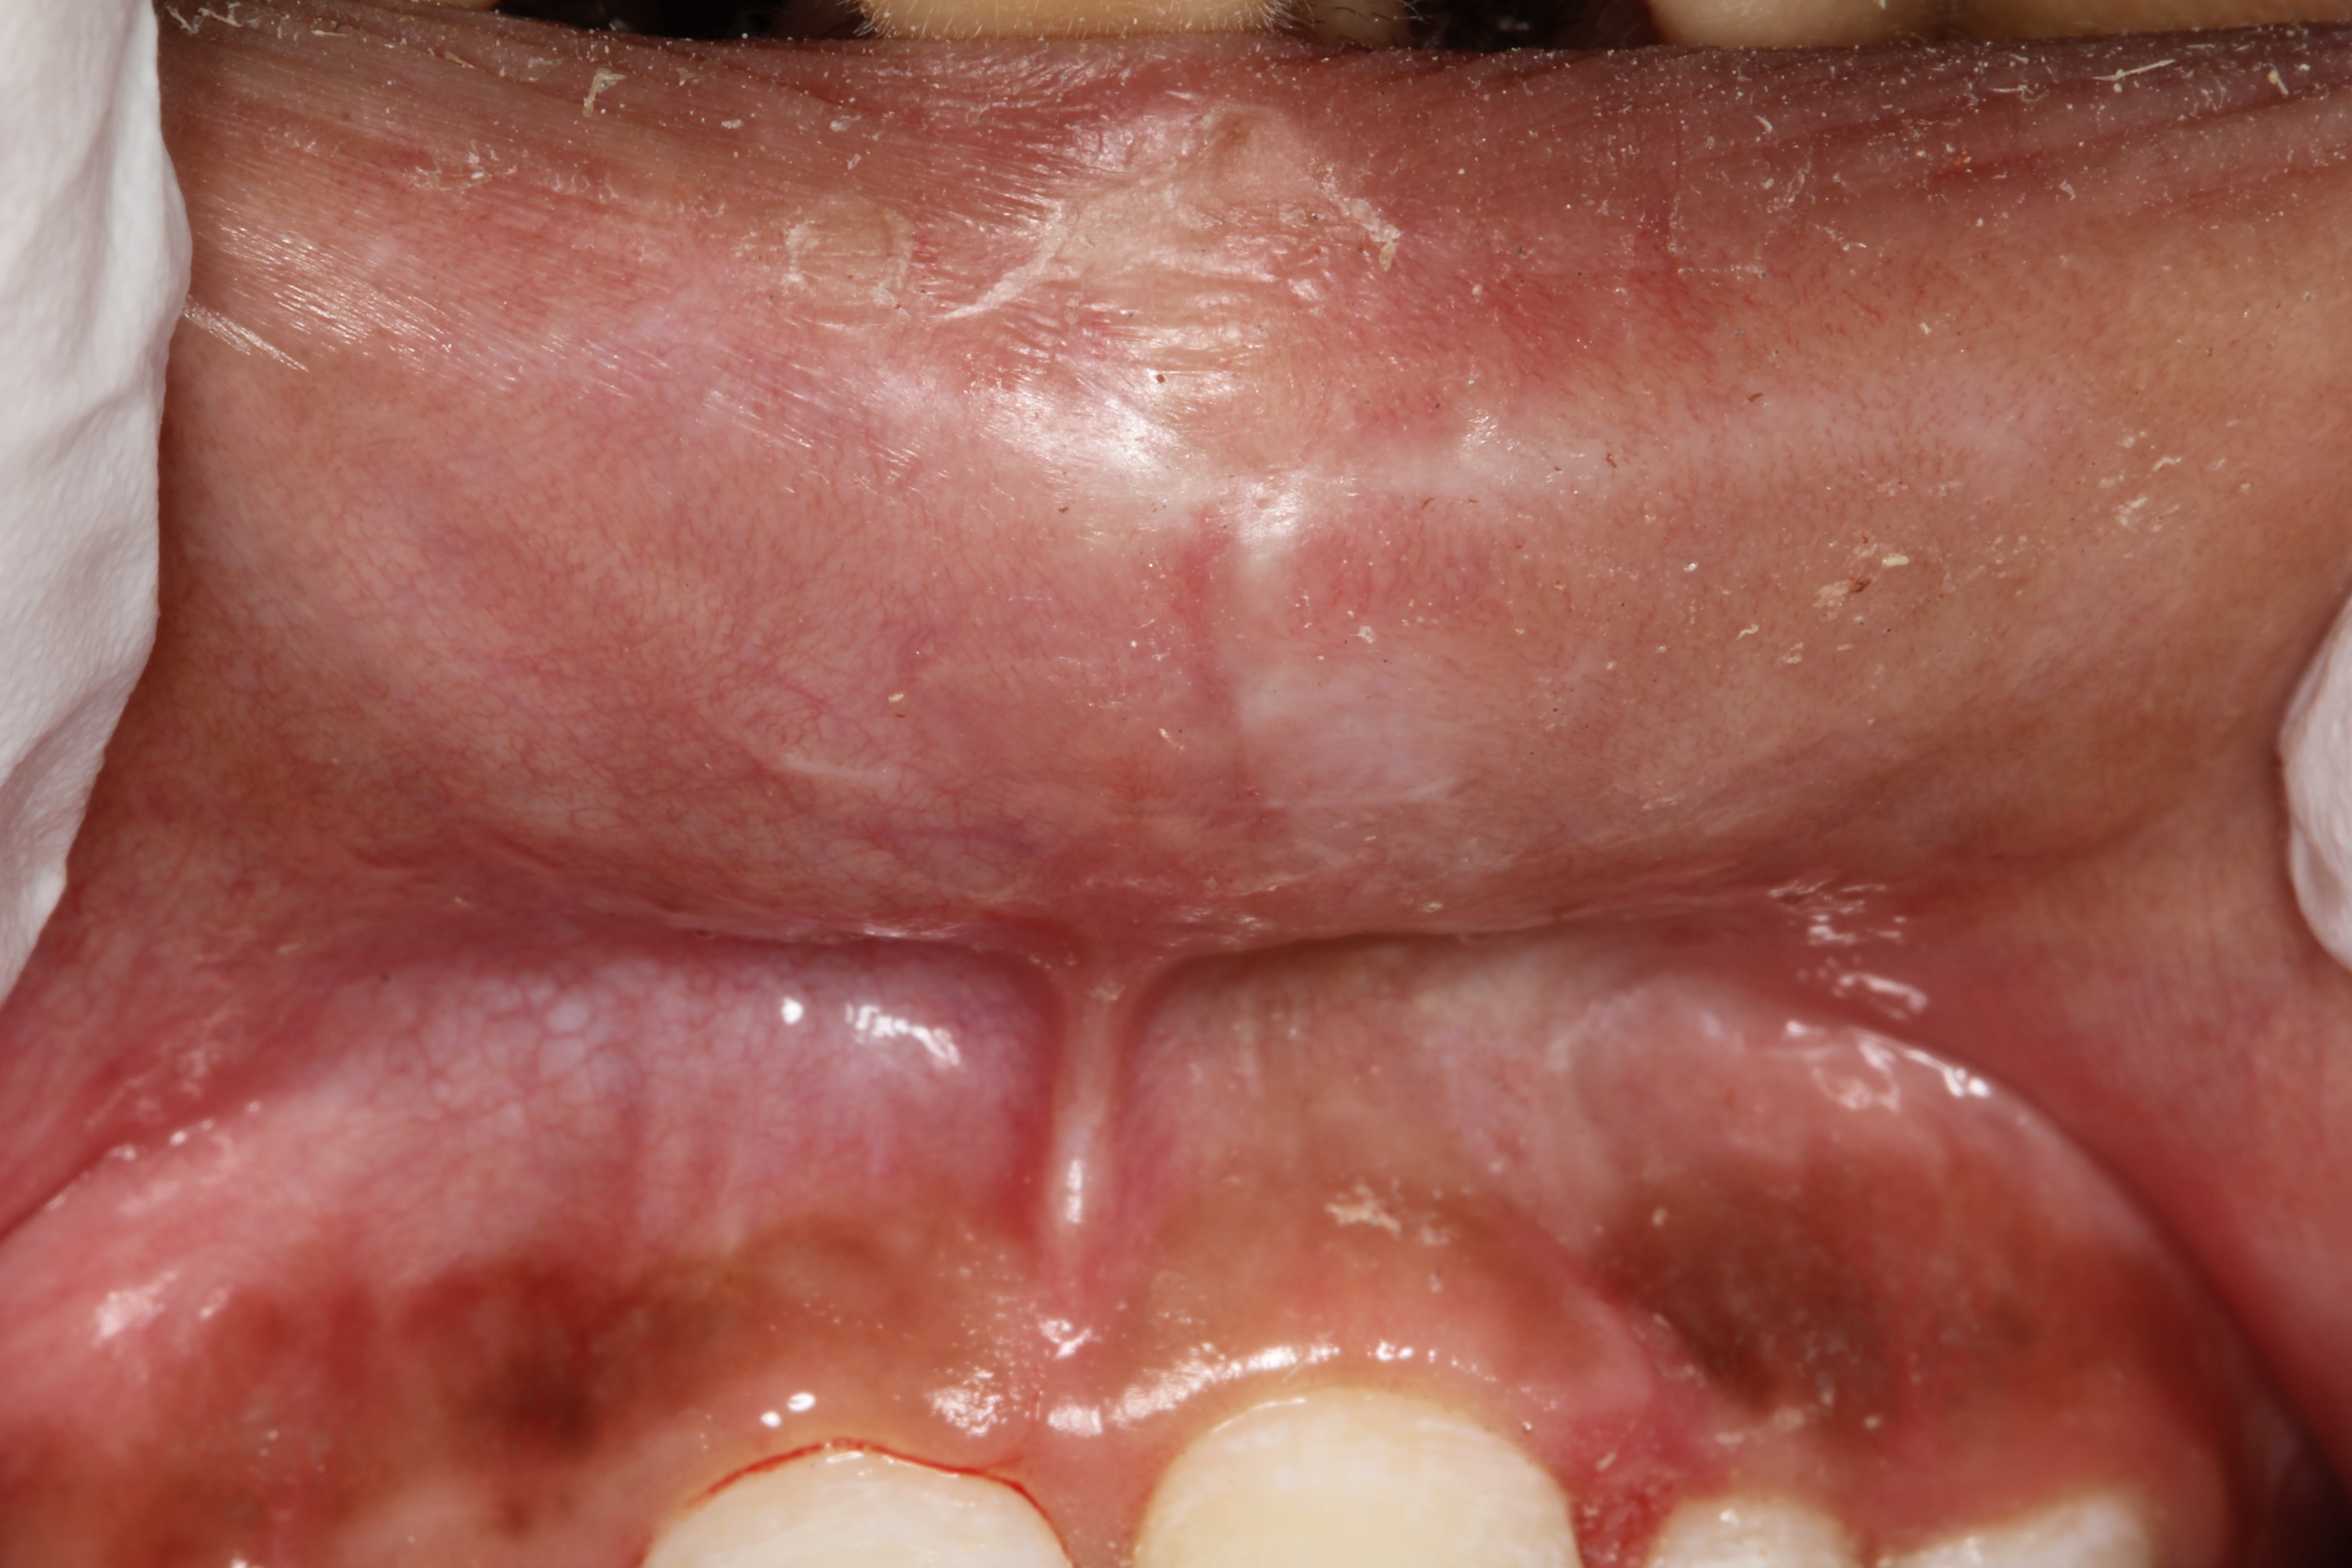

Petit cas clinique d'un traumatisme avec expulsion de 21 sur un enfant de 11 ans et 10 mois.

- 12/22 concussion - 11 subluxation - 21 expulsion

- lacération de la lèvre supérieure